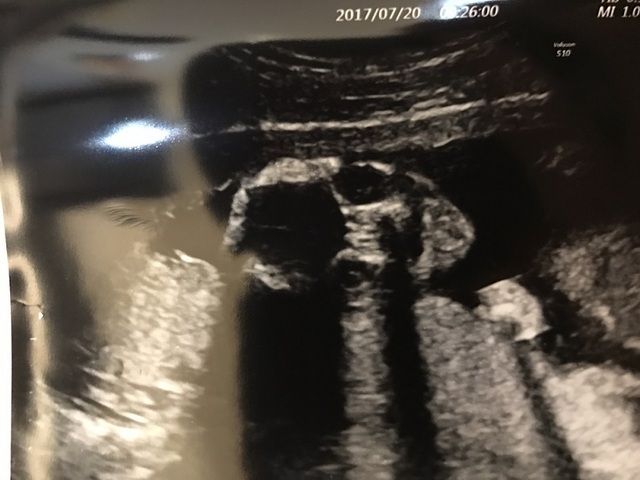

17週4日(17w4d・男の子)|のじこ さん(23歳)

エコー写真撮影時のエピソード:

つわりが長く続いていて、起き上がるのもつらかったです。お米が炊ける匂いで気持ち悪くなり、温かいものが食べられなくなったためサンドイッチばかり食べてました。妊娠初期から目眩がひどく、病院で症状を伝えましたが、血液検査では異常なしでした。妊娠後期には症状が治まりました。この写真で初めて足の形がはっきりわかり、とてもうれしかったのを覚えています。